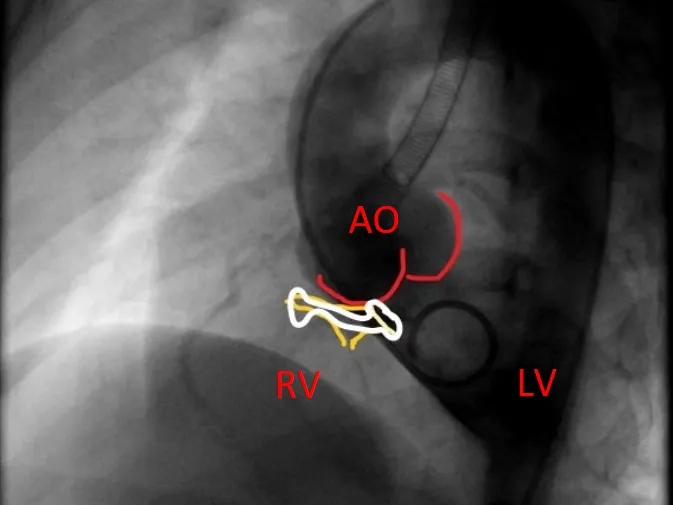

左右盘展开后,封堵器未锁定时造影可见封堵器中间少量反流,主动脉瓣少量反流。

牵拉成型线锁定后,分流消失,主动脉瓣反流消失。

封堵器锁定后呈“蝴蝶状”明显盘状形态,室水平分流完全消失,主动脉瓣反流消失。

锁定后牵拉及释放